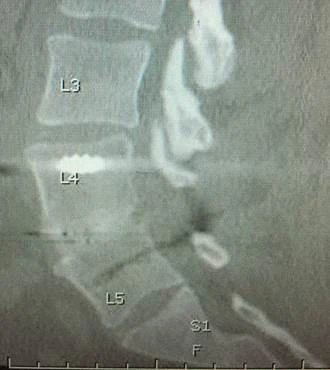

Lendenwirbelsäulenfusion mit Käfig aus PEEK-OPTIMA HA Enhanced

Timothy Bassett, MD von SouthEastern Spine Specialists, Tuscaloosa/USA, präsentierte seine ersten Anwendungserfahrungen mit Lendenwirbelsäulenkäfigen aus PEEK-OPTIMA HA Enhanced. Im TLIF-Verfahren (Transforaminal Lumbal Interbody Fusion) über ein bis zwei Wirbelbereiche wurde EVOS-HA, ein Implantat des Unternehmens Cutting Edge Spine eingesetzt, das zur Verwendung bei Patienten mit ausgewachsenem Skelett bei der Lendenwirbelsäule vorgesehen ist. Die Cages waren mit patienteneigenem Knochenmaterial gefüllt und wurden mit posteriorer Instrumentierung eingesetzt, bei den insgesamt neun Patienten wurden keine biologischen Präparate verwendet. Die klinischen Ergebnisse wurden bewertet in Bezug auf Schmerzen auf einer visuellen Analogskala (VAS), den Einsatz von Opiaten, neurologische Funktion, wiederholte Operationen und Komplikationen. Die Fusionsergebnisse wurden nach Durchführung von anteroposteriorem (AP) und lateralem Röntgen nach sechs und zwölf Wochen sowie einem CT-Scan nach sechs Monaten beurteilt.

Dr. Bassett fasst die Ergebnisse zusammen:„ Röntgenergebnisse nach sechs Wochen zeigen die sehr schnell sichtbare Knochenfusion zwischen den Wirbeln. Damit korrespondieren gute klinische Resultate, wie keine neurologischen Folgen über sechs Wochen hinaus, keine Implantat¬migrationen, keine Absenkung und keine Pseudoarthrosen. Noch wichtiger war, dass sich bei der CT-Kontrolle nach sechs Monaten neun von zehn Fusionen mit patienteneigenem Knochen als definitiv stabil erwiesen, trotz teils sehr schwieriger Patientensituation. Auch bei dem Patienten, der keine vollständige Fusion aufwies, schritt die Fusion voran; der Fusionsprozess wurde durch Rauchen einer Packung Zigaretten täglich, sowohl vor als auch nach der Operation, beeinträchtigt.“

Bildunterschrift:

Stabile Lendenfusion nach sechs Monaten unter CT-Bild mit EVOS-HA Lumbar Interbody System der Firma Cutting Edge Spine. Bild wurde mit freundlicher Genehmigung von Timothy Bassett, MD, zur Verfügung gestellt.